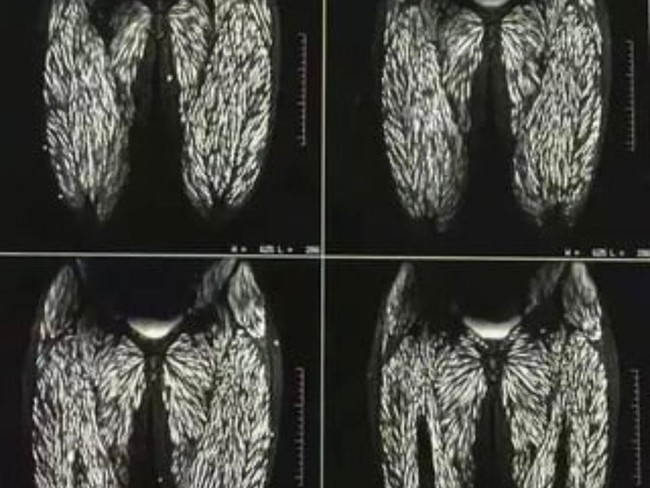

Foto: X @PicturesFoIder

Belakangan ini ramai di media sosial kolase foto rontgen tubuh manusia yang dipenuhi parasit. Foto tersebut viral setelah diunggah oleh akun X @PicturesFoIder (22/08/24).

Dalam klaimnya, tubuh wanita itu mengalami infeksi parasit akibat sering makan daging babi mentah selama 10 tahun. Unggahannya viral hingga di mendapat view 38.2 juta.

Serangkaian gambar medis tersebut tersebar di berbagai platform media sosial pada Agustus 2024. Konon, itu merupakan tubuh seorang wanita berusia 23 tahun asal China.

"Tubuh wanita ini penuh parasit karena sering makan daging babi mentah selama 10 tahun," bunyi unggahan tersebut.

Dikutip dari Snopes (12/09/24) ada informasi yang benar dan ada pula yang salah pada berita tersebut. Memang fakta bahwa rontgen itu memperlihatkan bagian tubuh seorang wanita.

Itu merupakan rontgen tubuh bagian bawah dan kaki yang benar terinfeksi parasit akibat seringnya makan daging babi mentah. Foto rontgen itu diambil ketika si wanita masih berusia 23 tahun.

Saat itu, dilaporkan bahwa wanita tersebut memang selalu makan daging babi mentah sejak usia 10 tahun.